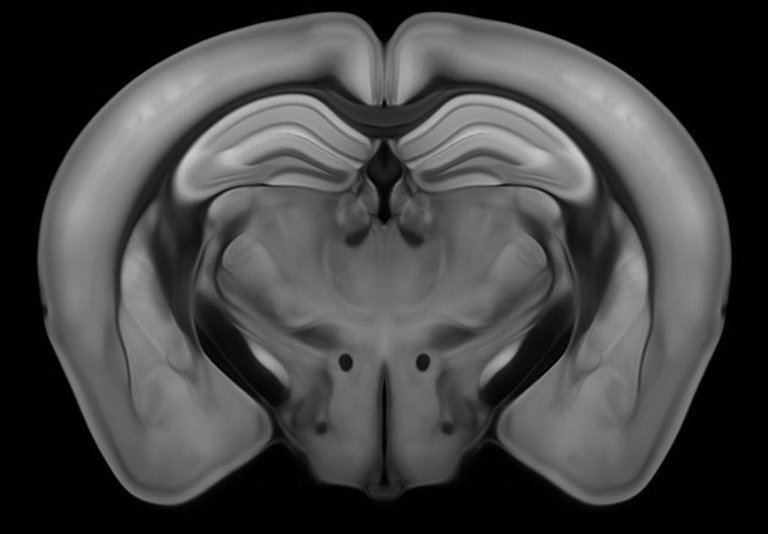

Para conocer mejor los mecanismos que provocan la adicción, los autores del artículo han realizado experimentos con los ratones. Así, primero les dieron fentanilo y vieron que el fentanilo actúa sobre la zona tegmental ventral del cerebro (VTA): desinhibe las neuronas de la dopamina y libera dopamina en el núcleo accumbens. Si se inactivan los receptores opioides de VTA, observaron que se interrumpe la emisión de dopamina y se anula el efecto positivo, pero que el síndrome de abstinencia no desaparece.

Así, en el siguiente paso, los investigadores identificaron las neuronas de los receptores opiodes activados en el síndrome de abstinencia en la zona central de la amígdala (CeA). La desactivación de estos receptores hizo desaparecer los síntomas del síndrome de abstinencia. Así han demostrado ser responsables del refuerzo negativo. Estos resultados han sido confirmados por optogenética.